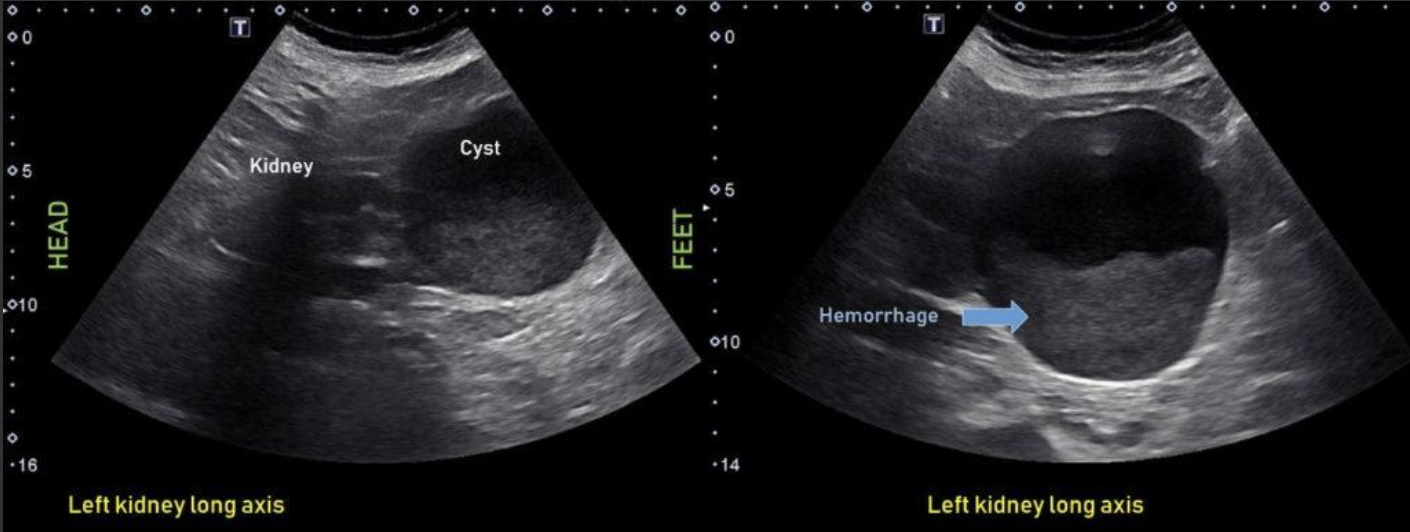

Complex Renal Cyst → any cyst that is not a simple cyst

clinical hx: post-surgery, trauma

s/sx: flank pain, fever, hematuria, WBC increase, can be asymptomatic

2D US: well-defined cystic structure, internal echoes or anechoic, septations, focal hypoechoic inner mural extension, can be hemorrhagic

color doppler: if solid can have vascularity

DDX: malignant tumor, RCC